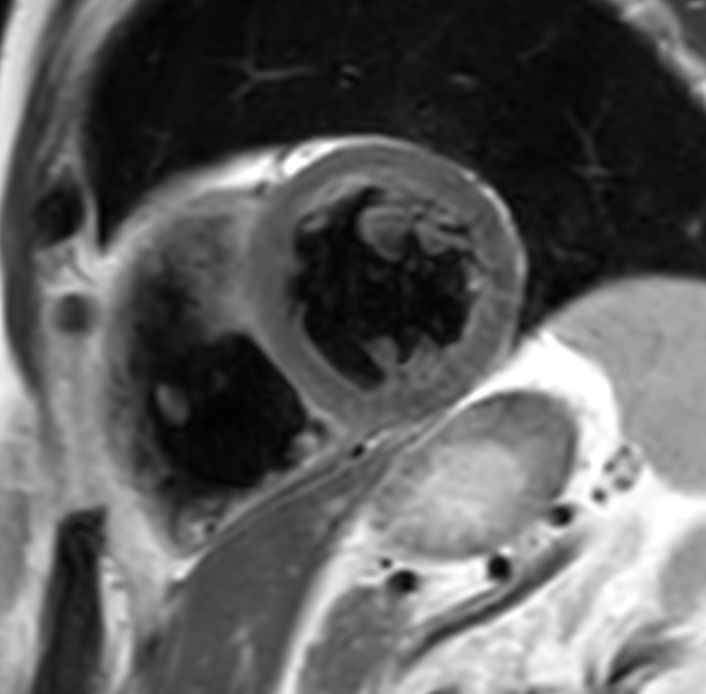

bTFE short axis Without Compressed SENSE: 8.4 sec breath hold

-

bTFE short axis With Compressed SENSE: 4.8 sec breath hold